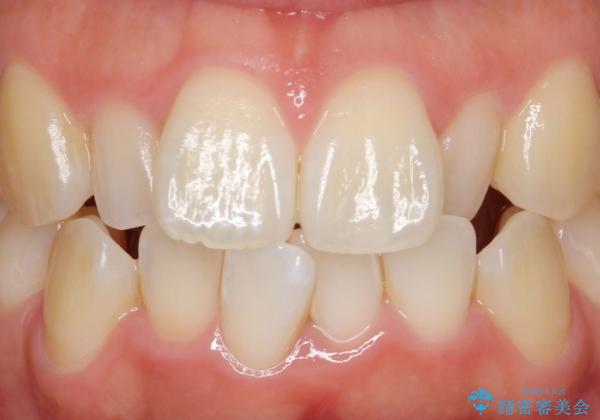

自然な仕上がりにご満足頂けました。

「自分でもどこを治したのかわからないくらい自然!」と喜んで下さいました。

クラウンの種類:オールセラミッククラウン スペシャル